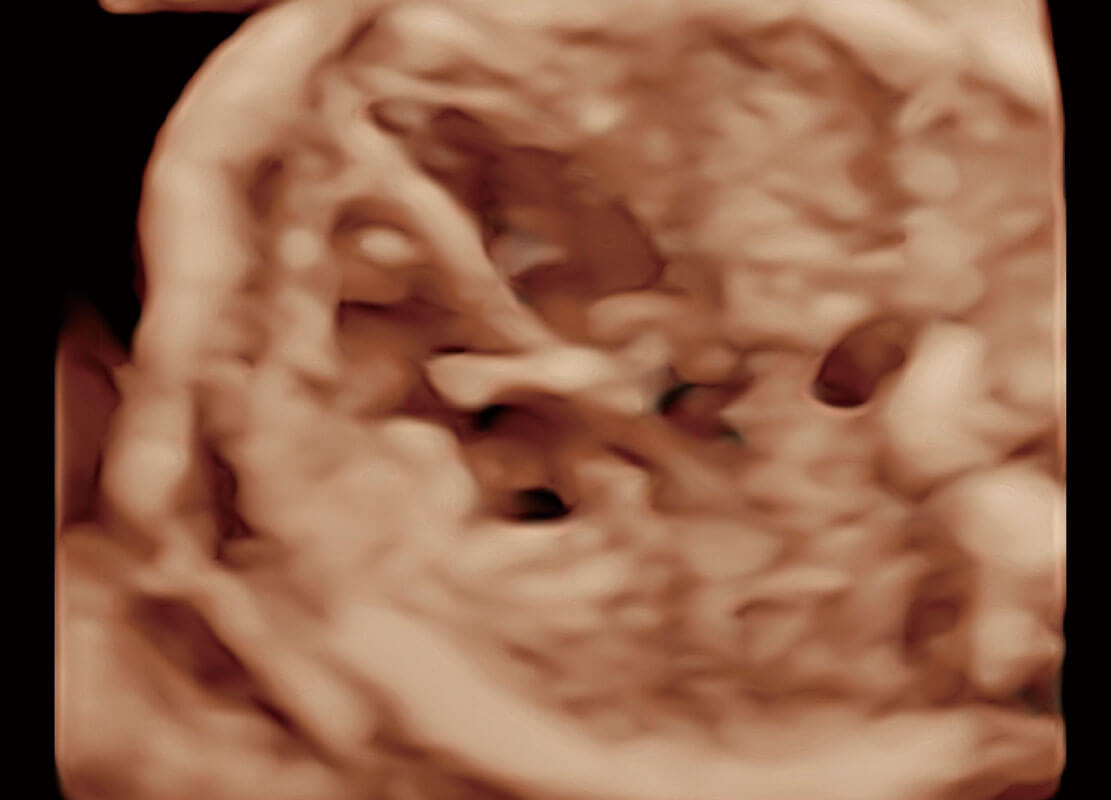

腔内三维-光影成像